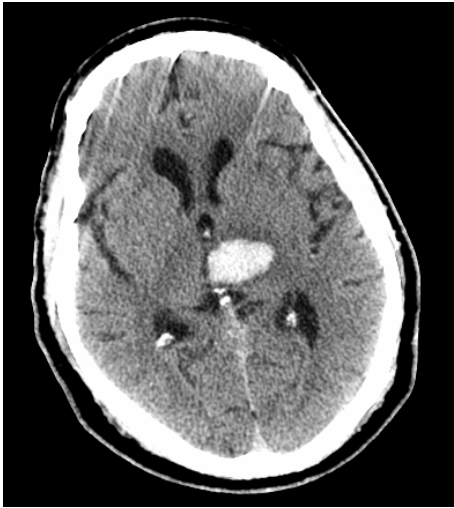

• CT is attached

What part of the brain is affected?

Left Thalamus (& Left Internal Capsule)

What type of lesion is this?

Hemorrhagic Stroke (Recall: Hemorrhage is bright on CT!)

What vessel was affected by the lesion?

Small lacunar vessels (Again, think deep structures of the brain for lacunar stroke)

What underlying factors likely caused the lesion?

Hyaline arteriolosclerosis & Hypertension